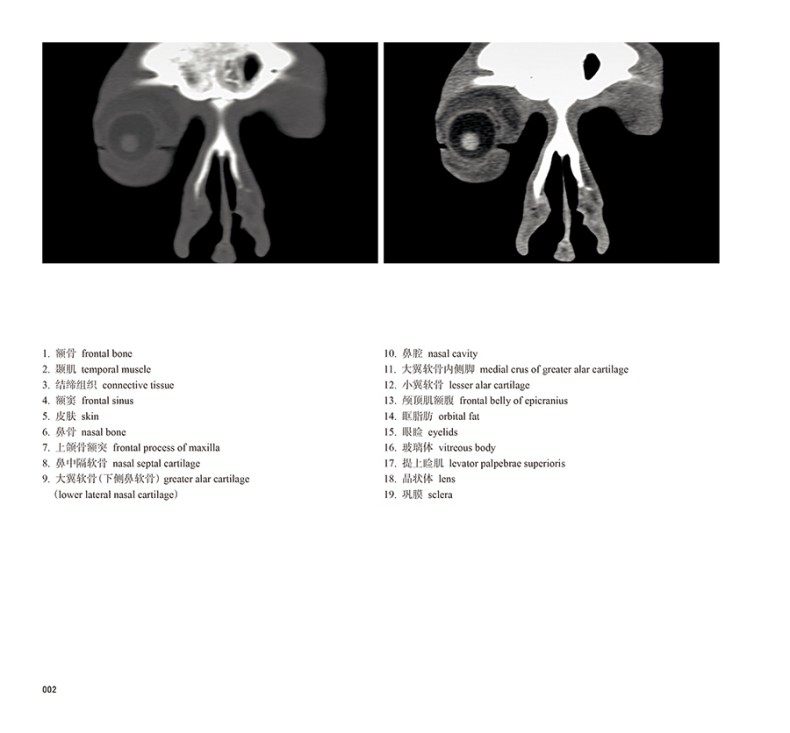

本书从数据集每隔1.2mm选取一幅图像,截取眼、耳、鼻及毗邻颅底的局部区域图像,共112幅图像。同时配以相应部位的CT图像对照。本书特色是断层解剖图利用数字图像处理技术优势,放大并清晰展示眼、耳、鼻及毗邻颅底断面的局部区域结构,组织色泽真实,甚至能够清晰显示肌肉纹理、筋膜纹路等细节结构,图像质量高于美国《人体断层解剖学彩色图谱》(引进版)类似图谱图像质量。对眼科、耳鼻咽喉科医生理解相关解剖结构有较大帮助。